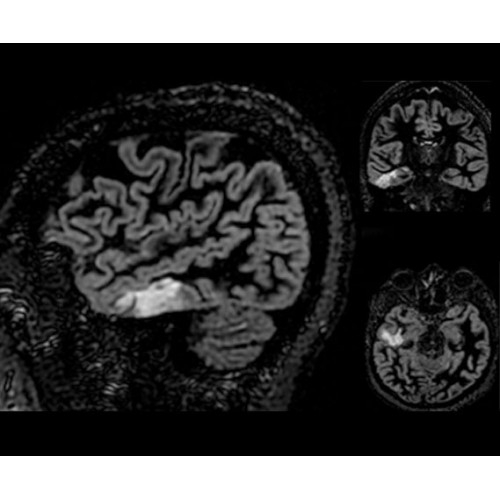

SIGNA Architect 3.0T — это новейший МРТ аппарат компании GE, который предлагает высочайший уровень производительности — в системе 128 приемных каналов, 48 канальная катушка головы, полный спектр клинических возможностей. Высокий уровень комфорта пациента обеспечивают такие особенности как отсоединяемый стол, положение пациента «ногами вперед» для всех видов исследований, SilentWorks — бесшумное и MAGIC — быстрое сканирование.

Теперь возможности МРТ поражают еще больше благодаря ультрасовременным решениям для визуализации с SIGNA Architect 3.0 Тл, объединяющей новейшие достижения в области МР-технологий и интуитивно понятный интерфейс. Система SIGNA Architect, разработанная на базе новой платформы SIGNA Works, представляет собой гармоничное сочетание дизайна и функциональности. Каждый элемент системы направлен на повышение производительности, эффективности клинической практики, финансовых показателей, а также комфорта и безопасности пациента.

• NeuroWorks — универсальное решение для визуализации анатомии головного мозга, позвоночника, сосудов и периферических нервов с четкой дифференциацией тканей.

• 48-канальная катушка TDI для головы, входящая в базовую комплектацию SIGNA Architect, обеспечивает феноменальную производительность с учетом особенностей каждого пациента. Благодаря гибкому и универсальному дизайну, высокому соотношению сигнал/шум и передовым технологиям визуализации, таким как HyperWorks, учитываются потребности подавляющего большинства пациентов.